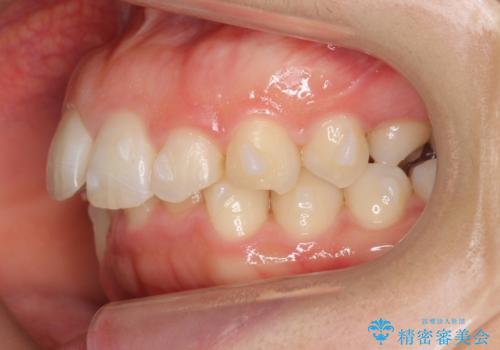

- 前歯のがたがたと出っ歯を主訴に来院。

CTを撮影したところ、臼歯部の頬側の骨の厚みが非常に大きく、通常では考えられない量の歯列の拡大が可能でした。

今回は健康を損なわずに非抜歯で治療が可能でしたが、

歯ぐきや骨の厚みが薄い他の患者さんでは難しいです。

左上5は180度捻転していましたので、そのまま並べています。

遠心移動などは行わず、IPRと拡大のみで治療を行いました。

一般的に非抜歯矯正を無理に行うと、口元がモッコリ出てしまうことがあります。しかし、今回は前歯を前に出さないような設定にしており、口元が出ることもありませんでした。